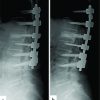

An elderly male presented with OVF of the L1 (with a bone mineral density showing a T-score of −3.7) of 3 weeks history with a pain in the back and intact neurology. The pain was severe with a visual analog score (VAS) scale 7/10 that was mechanical in nature aggravated with tuning on bed and on loading of spine. The X-ray showed a fracture of D12 and L1 (Fig. 1a) and it was confirmed on the magnetic resonance imaging (MRI) showing an acute fracture (Fig. 1b). He was planned for stentoplasty (VBS System, DePuy Synthes, Johnson & Johnson) at L1 and vertebroplasty at D12. The patient was positioned prone and given me an erector spine block at D11 level for the case. The field was sterilised and draped. A wide trocar (number 7) was railroaded over the guide wire pins. The guide wires were removed, a drill was passed in the trocar (Fig. 2a), and an impactor was placed to create the void (Fig. 2b). Nest, balloon was inserted inside and inflated (Fig. 2c), but beyond 22–25 atm (atmospheric pressure), the device was turning “false” and returned to zero. It happened on both sides and on both devices. The balloon was tested outside and found to be working adequately. The stent-mounted balloon was next inserted (Fig. 2d), and after a partial inflation on the left side, the stents did not expand. The right-side stent and balloon could not be inflated. The cement inserter failed to pass through the trocar; vertebroplasty was done on either side of the stent and also on the right side (Fig. 2e-f). At the proximal D12 level, vertebroplasty was done (Fig. 2g-h). Post-procedure, the neurology of the patient was intact. The post operative x-ray was satisfactory (Fig. 1c) and patient discharged next day after mobilisation. He had tremendous relief of pain (VAS of 1/10).